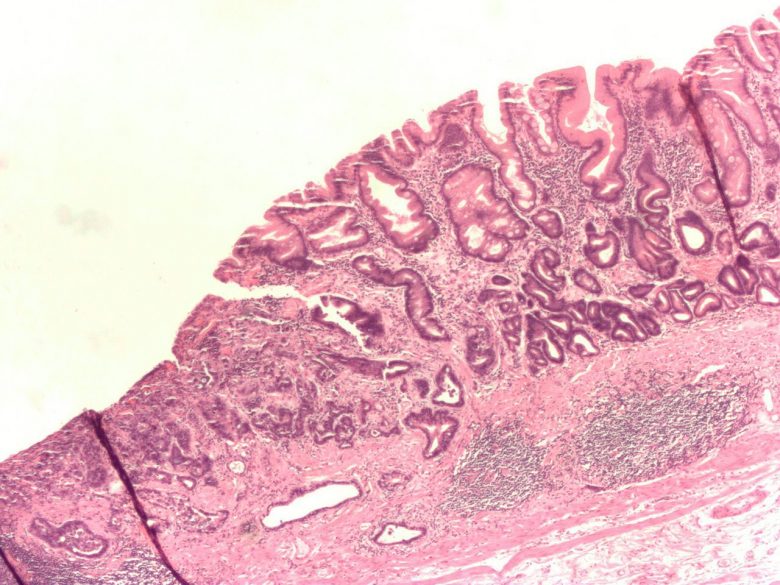

Small intestine cancer

“Small intestine cancer usually begins in an area of the intestine called the duodenum. This cancer is rarer than cancers in other parts of the gastrointestinal system, such as the colon and stomach.

“The types of cancer found in the small intestine are adenocarcinoma, sarcoma, carcinoid tumors, gastrointestinal stromal tumor, and lymphoma.

“Diet and health history can affect the risk of developing small intestine cancer. Signs and symptoms of small intestine cancer include unexplained weight loss and abdominal pain. Tests that examine the small intestine are used to detect (find), diagnose, and stage small intestine cancer.”

Image Credit: Nephron / Wikimedia Commons.